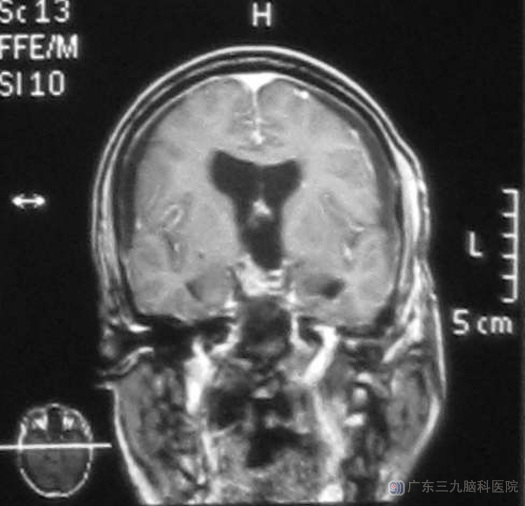

近半个月,培叔觉得有点头痛,视力也开始下降,大哥建议他去医院检查一下。头颅CT检查提示:鞍区占位,考虑颅咽管瘤的可能性大。在广东三九脑科医院进一步检查,头颅MR提示病变大小约5.4cm×4.3cm×4.3cm。

综合神经外科 鲁明主任主刀,在全麻下行经额右侧纵裂入路鞍上三脑室肿瘤切除术,显微镜下见肿瘤位于鞍上,呈灰白色,用双极电凝并肿瘤分块切除,对下丘脑、垂体柄及重要血管保留完整,手术顺利。现已康复出院,术后病理结果:颅咽管瘤。

颅咽管瘤是由外胚叶形成的颅咽管残余的上皮细胞发展起来的一种常见的胚胎残余组织肿瘤,为颅内最常见的先天性肿瘤。颅咽管瘤压迫下丘脑及垂体还可引起多种内分泌代谢紊乱和下丘脑功能障碍,肿瘤破坏视上核或神经垂体,可引起尿崩症,患者每天饮水在3000~4000ml以上。

颅咽管瘤最常见的部位是在鞍区,属于颅脑的中心地带,位置深,并且周围有视神经、颈内动脉、大脑前动脉、垂体、下丘脑等主要结构,常常与下丘脑粘连,手术视野狭小深在,手术难度很大。http://www.999brain.com/